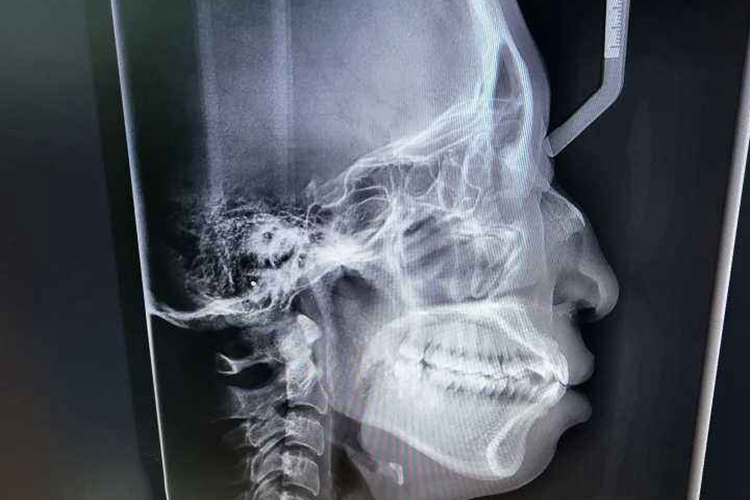

牙齿咬合指牙齿接触,牙齿咬合关系指咀嚼时牙齿接触关系,牙齿咬合关系分为正中咬合和非正中咬合,X光即X线片表现有所差异。

牙齿咬合关系分为正中咬合和非正中咬合,非正中咬合又分为前伸咬合及侧咬合,X线片表现有所差异。